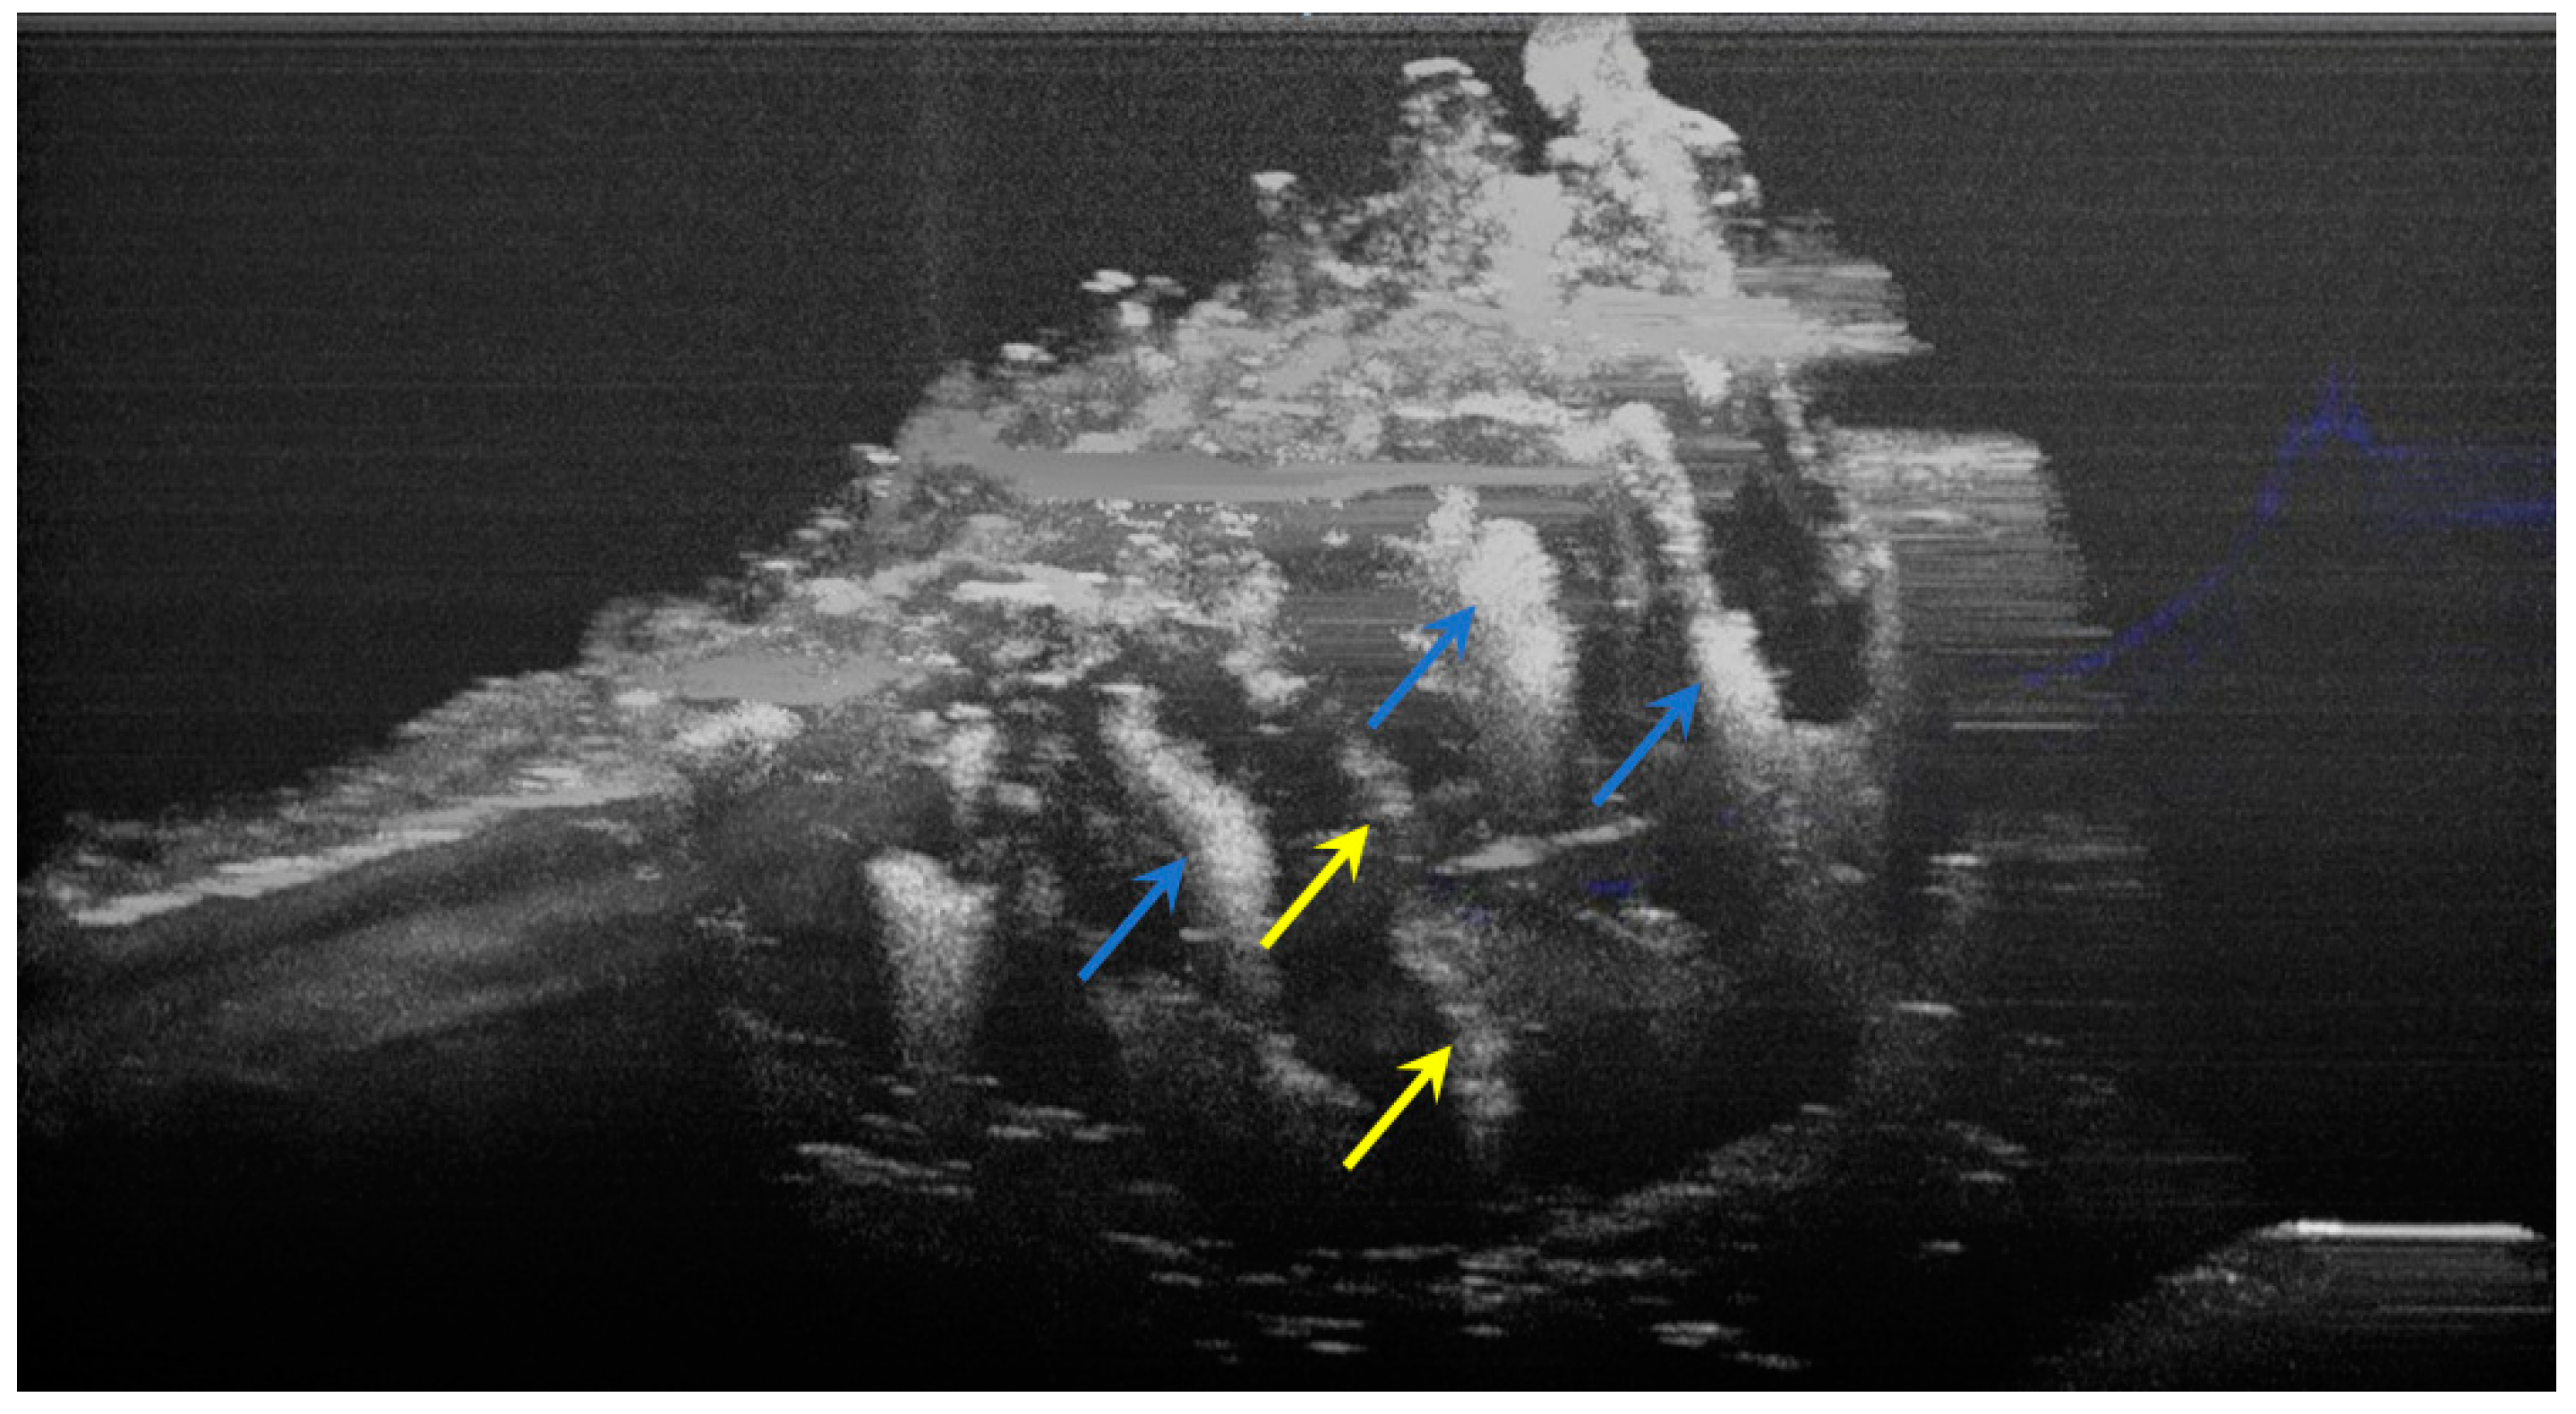

The image processing using ImageJ software showed the spatial disposition and extent of the hypomineralization lesions and hypoplasia (Figure 6, Figure 7, Figure 8 and Figure 9).

Figure 6.

Three-dimensional OCT reconstruction of hypomineralization areas (Axis 0Y). The blue arrows indicate three well-defined areas; the yellow arrows indicate several small-size diffuse areas.